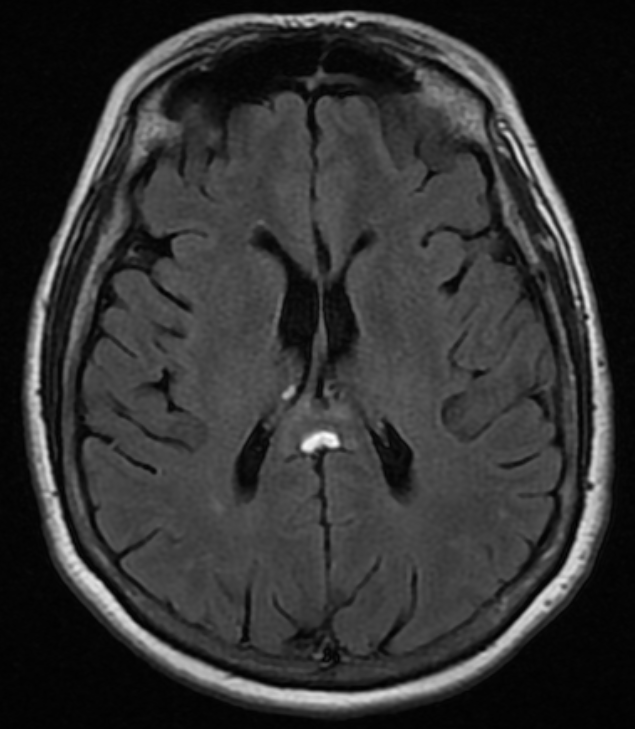

A middle aged woman was seen in the emergency department for confusion, and a non-enhanced head CT was obtained, shown below. Her exam was otherwise normal.

All three images above are non-enhanced head CT’s. First, locate the lesion – it is highlighted by a green arrow in the saggital, and by a blue arrow with bone windowing in the axial imaging. Where is it? What is the density compared to the surrounding brain tissue and CSF? Given the density, what should be in your differential diagnosis?

The answer is B) this is a lipoma. Only fat and air have a density below that of CSF on head CT. Although both lipomas and free air can look similar on normal brain windowing, by adjusting the image settings to bone windowing (middle image with blue arrow above), you will see that the lipoma is no longer totally dark.

Lipomas are relatively common, benign fatty tumors. They tend to be in the midline, just like this one is. They are usually developmental and rarely cause problems later in life – most of the time they are incidental findings like in this case. If large, they can disrupt the development of midline structures like the corpus callosum.